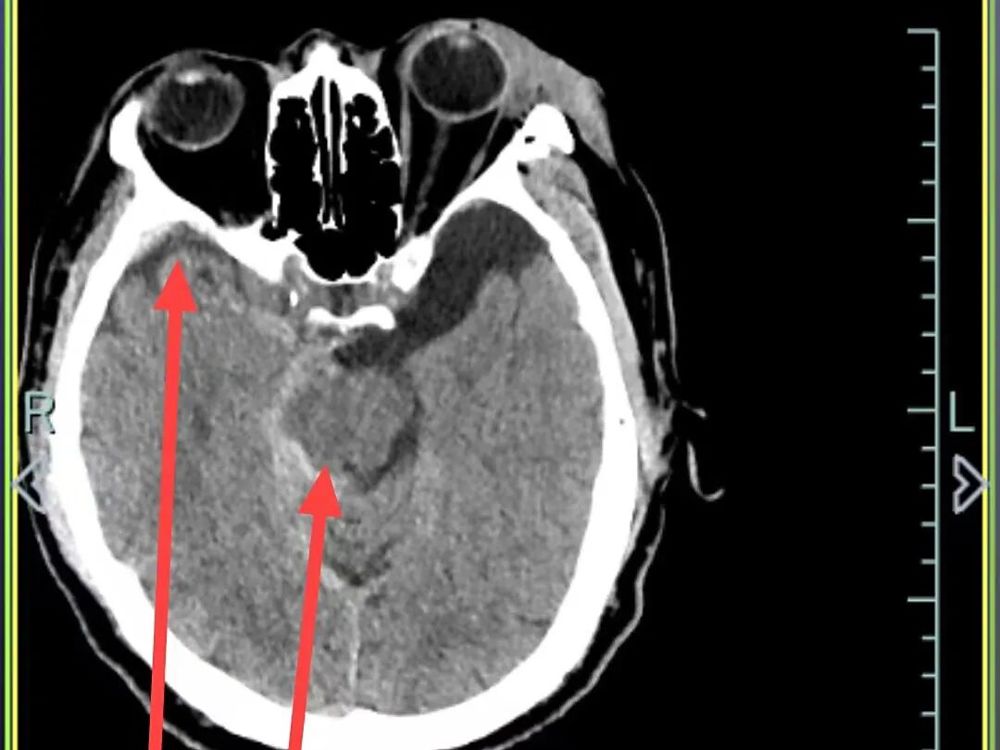

医院快速开通绿色通道并完善一系列检查后,诊断结果令人揪心:孙先生患有重型闭合性颅脑损伤,包括多发性创伤性脑出血、右侧颞部创伤性硬膜下出血、创伤性蛛网膜下腔出血以及脑震荡,同时合并多处骨折及软组织挫裂伤。

硬膜下出血、蛛网膜下腔出血和多发性创伤性脑出血

△10月4日CT复查显示,孙先生颅内出血全部吸收,骨折位置没有移位